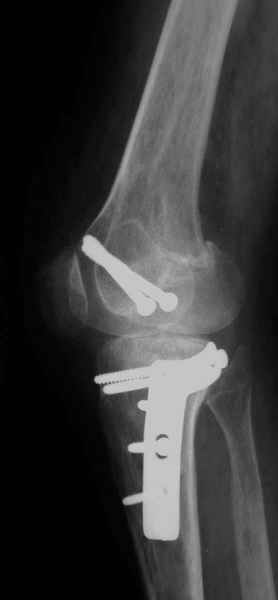

Как вариант решения прогрессирующей вальгусной деформации коленного сустава я бы предложил косую остеотомию дистального отдела бедра с фиксацией пластиной и компрессирующим винтом.

Около 5 лет применяю этот тип дистальной остеотомии бедра для коррекции механической оси Н/К ( более 20 случаев) - достаточно эффективная операция.

Было одно осложнение у молодого пациента - ятрогенное повреждение бедренной артрерии, которое решилось васкулярной пластикой без каких -либо последствий для функции конечности.